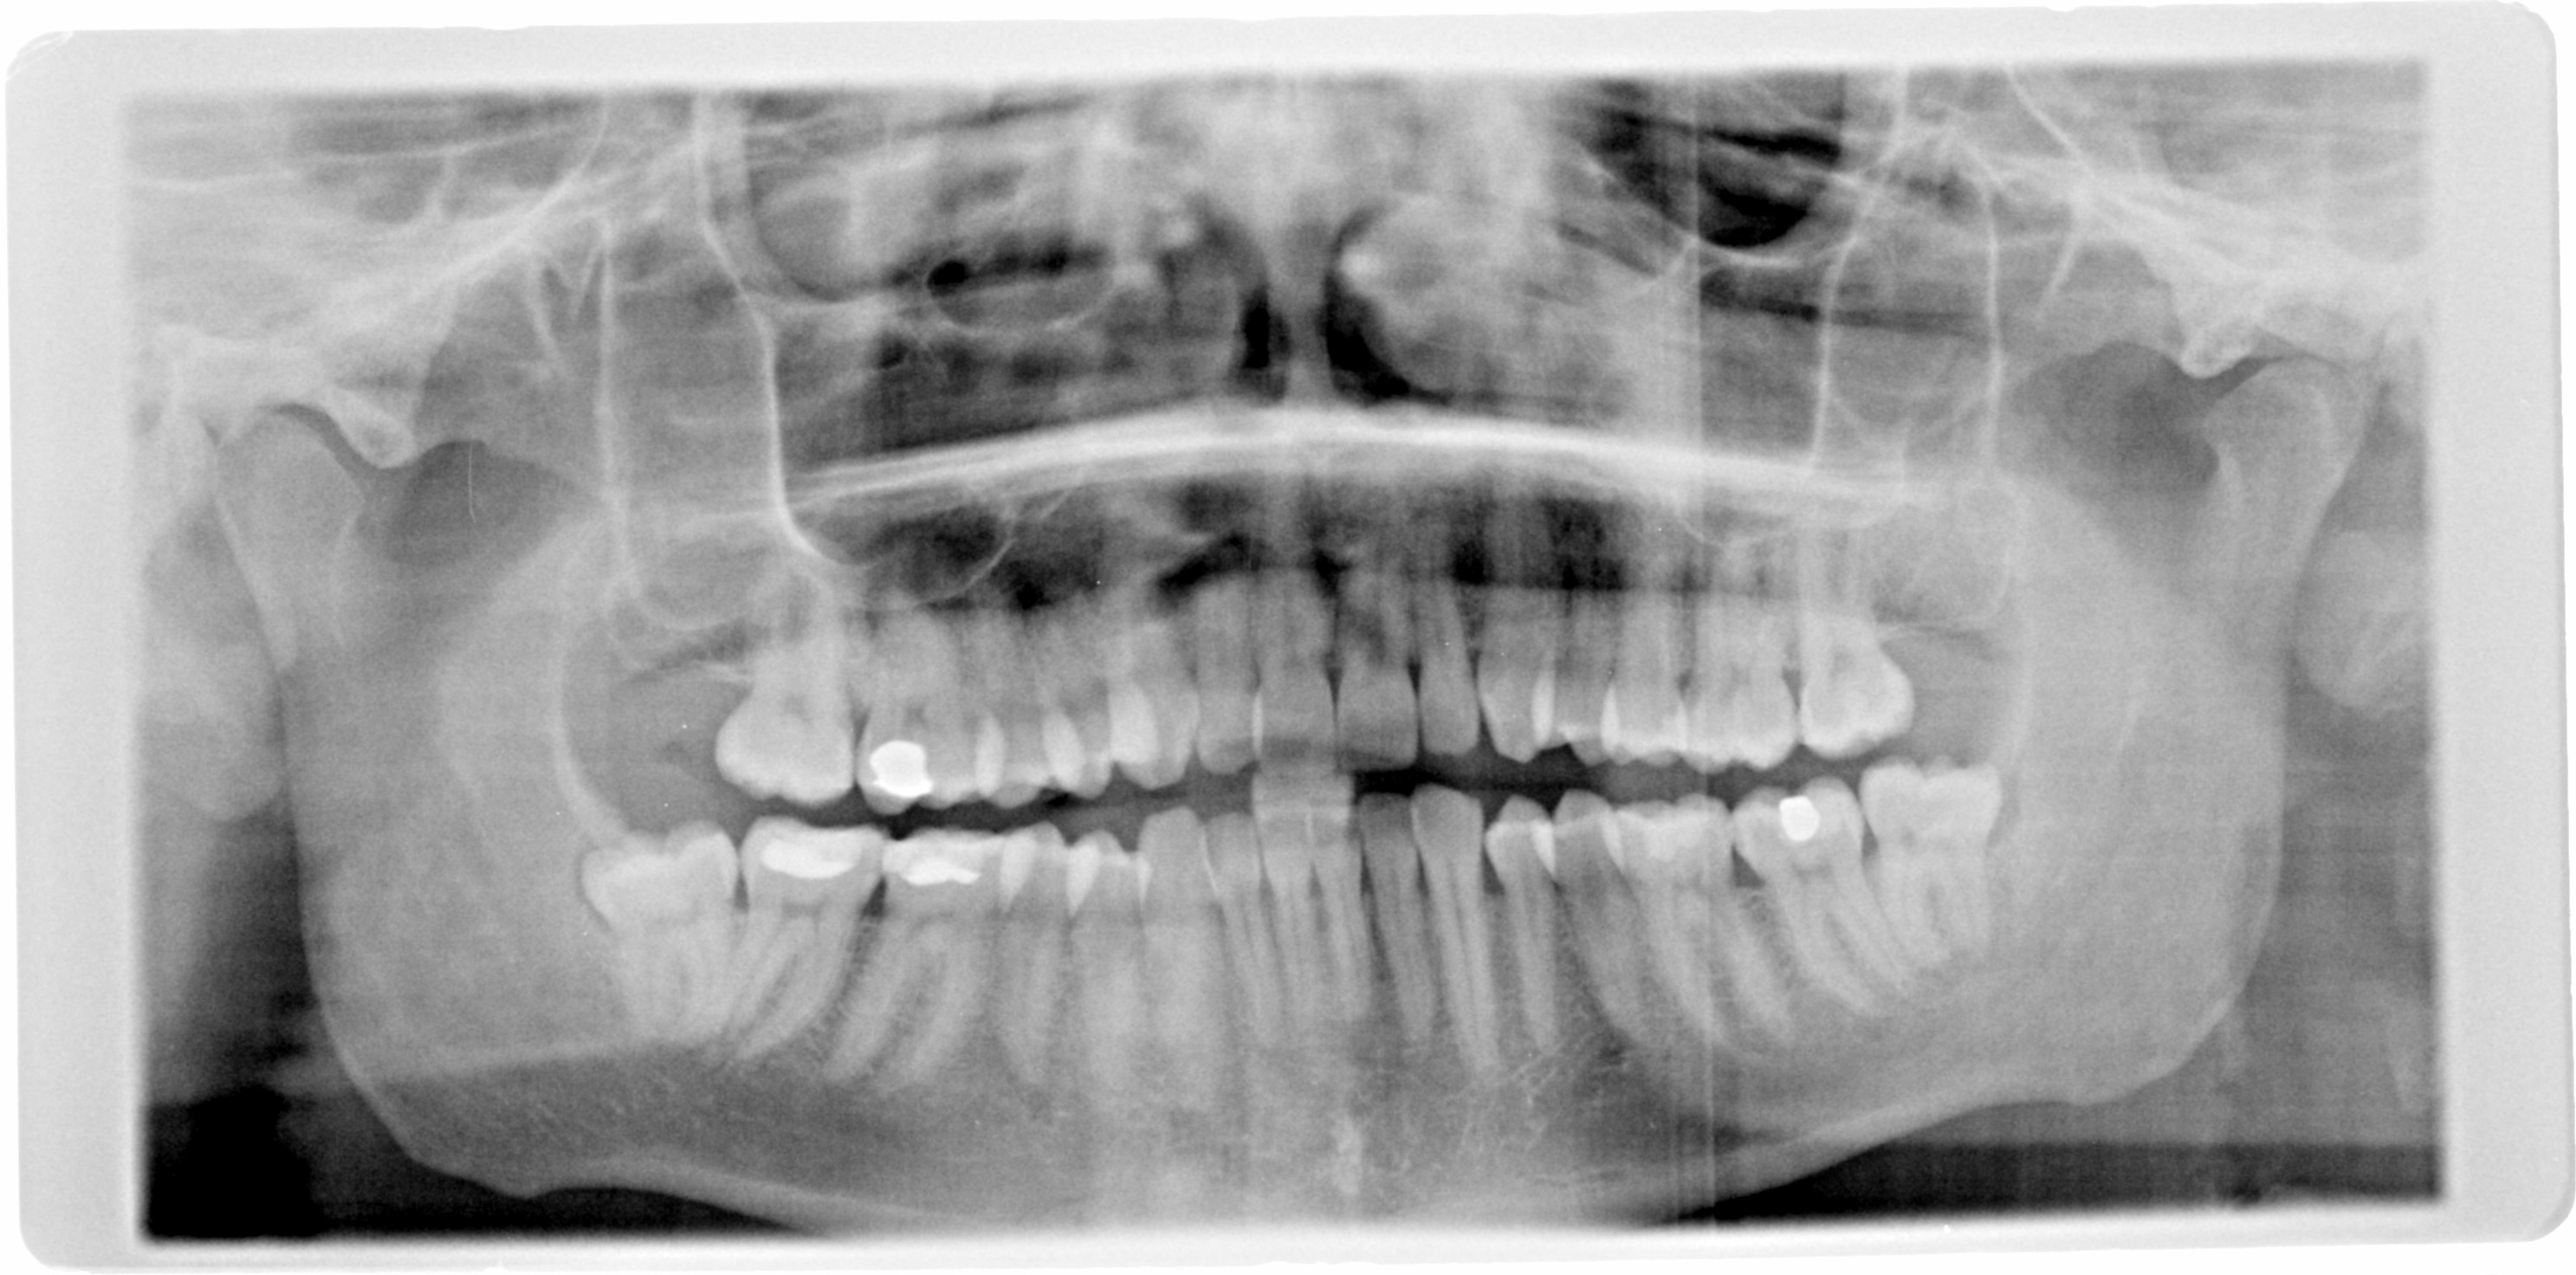

en nog even een fototje van mijn gebit als toegift. vlde week donderdag 2 kiezen trekken bij de kaakchirurg. wish me luck

even naar de OP kijkend zie ik geen groot paroprobleem.

Even een nieuwe mail sturen incl. ontvangstbevestiging en voor extra zekerheid een en ander ook nog in een aangetekende brief versturen. Hoe dan ook, bij een dergelijk bedrag is de tandarts ook verplicht jou op de hoogte te brengen van de hoogte van het bedrag en welles-nietes kan voor hem heel fout gaan aflopen als blijkt op de OPT dat de specialisten hier al zeggen dat dat niet aantoonbaar is.

Ik had wel willen zien of uit de status zou blijken dat er inderdaad sprake is van 26 x pocketdiepte > 4 mm?